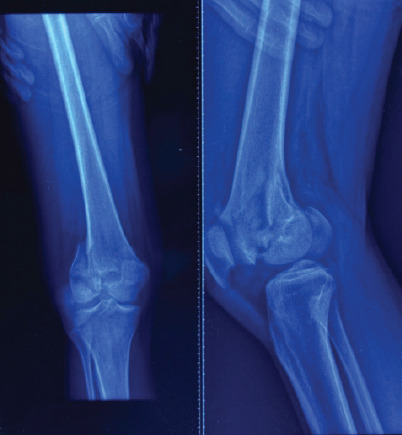

Case report: We present the case of a 25-year-old male who sustained an isolated bicondylar Hoffa fracture following a motorcycle accident. Radiographs and computed tomography (CT) imaging confirmed isolated coronal plane fractures of both femoral condyles (AO 33-B3), without metaphyseal comminution or intercondylar extension. The fracture was managed through a single medial parapatellar approach, using 5 cannulated screws and 2 headless Herbert screws. Post-operative rehabilitation involved early mobilization and progressive weight bearing. At 2 years follow-up, the patient demonstrated excellent functional recovery with a full range of motion (0-140°), no extensor lag, and pain-free full weight-bearing.